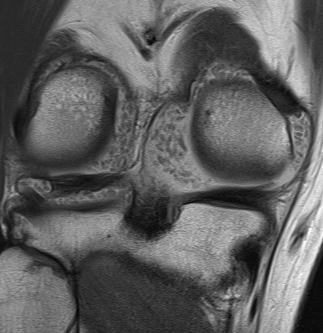

MRI

Synovial Proliferation

Soft tissue lesions same signal intensity as cartilage

Synovial chondromatosis

Synovial osteochondromatosis